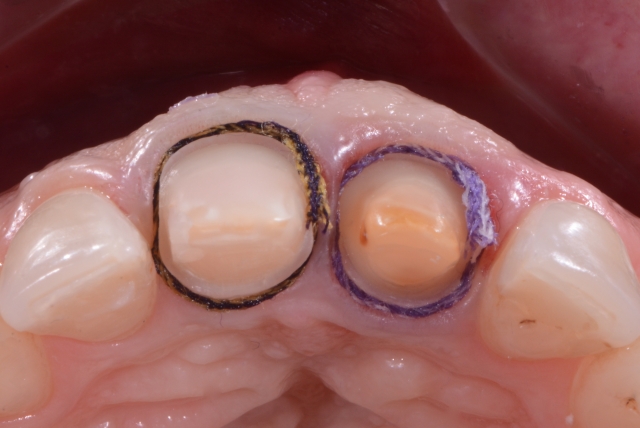

In cases where several abutments are to be imprinted, a definitive path of insertion and removal of the putty is mandatory to facilitate the tray’s reinsertion without distortions of the putty material. Proper parallelism between the prepared teeth is preferred for this technique, and no undercuts are present. To expose the margins of the preparation, a smaller-sized first cord was chosen (000 Ultrapack, Ultradent Products, Inc., USA).

After placing the first cord, an initial impression (putty material, Zhermack Spa Italy) of the prepared teeth was taken with a rigid stock tray.

The diameter of the second cord should be chosen according to the amount of deflection needed, considering the gingival biotype. Due to the difference in the positioning of the finishing line into the sulcus, two sizes for the second cords were chosen. Tooth #8 (11) being prepared for a full crown would need more deflection of the soft tissues to expose the preparation margin, so a #0 cord in size (Ultrapack, Ultradent Products, Inc., USA) was chosen. Tooth #9 (21) has been more minimally prepared for a veneer, so a thinner cord #00 would ensure the necessary deflection.